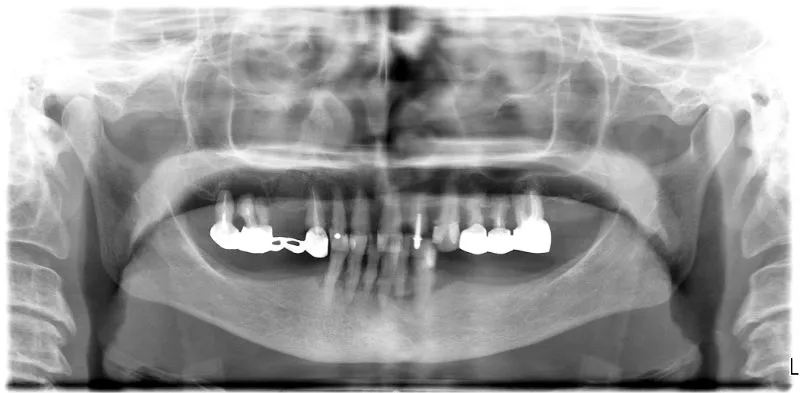

Ако Вие имате зъби, които подлежат на изваждане, ще се случи следното:

- Още същия 1-ви ден на оперативната интервенция ние ще премахнем зъбите и веднага, върху зъбни импланти, ще поставим временнен, неподвижен, винтово закрепен мост от 10 зъба.

- След 6 месеца ще сменим временния мост с постоянен, от 12 зъба – винтово закрепен, изработен по най-съвременна CAD/CAM технология от цирконий в нашата собствена зъботехнична лаборатория.